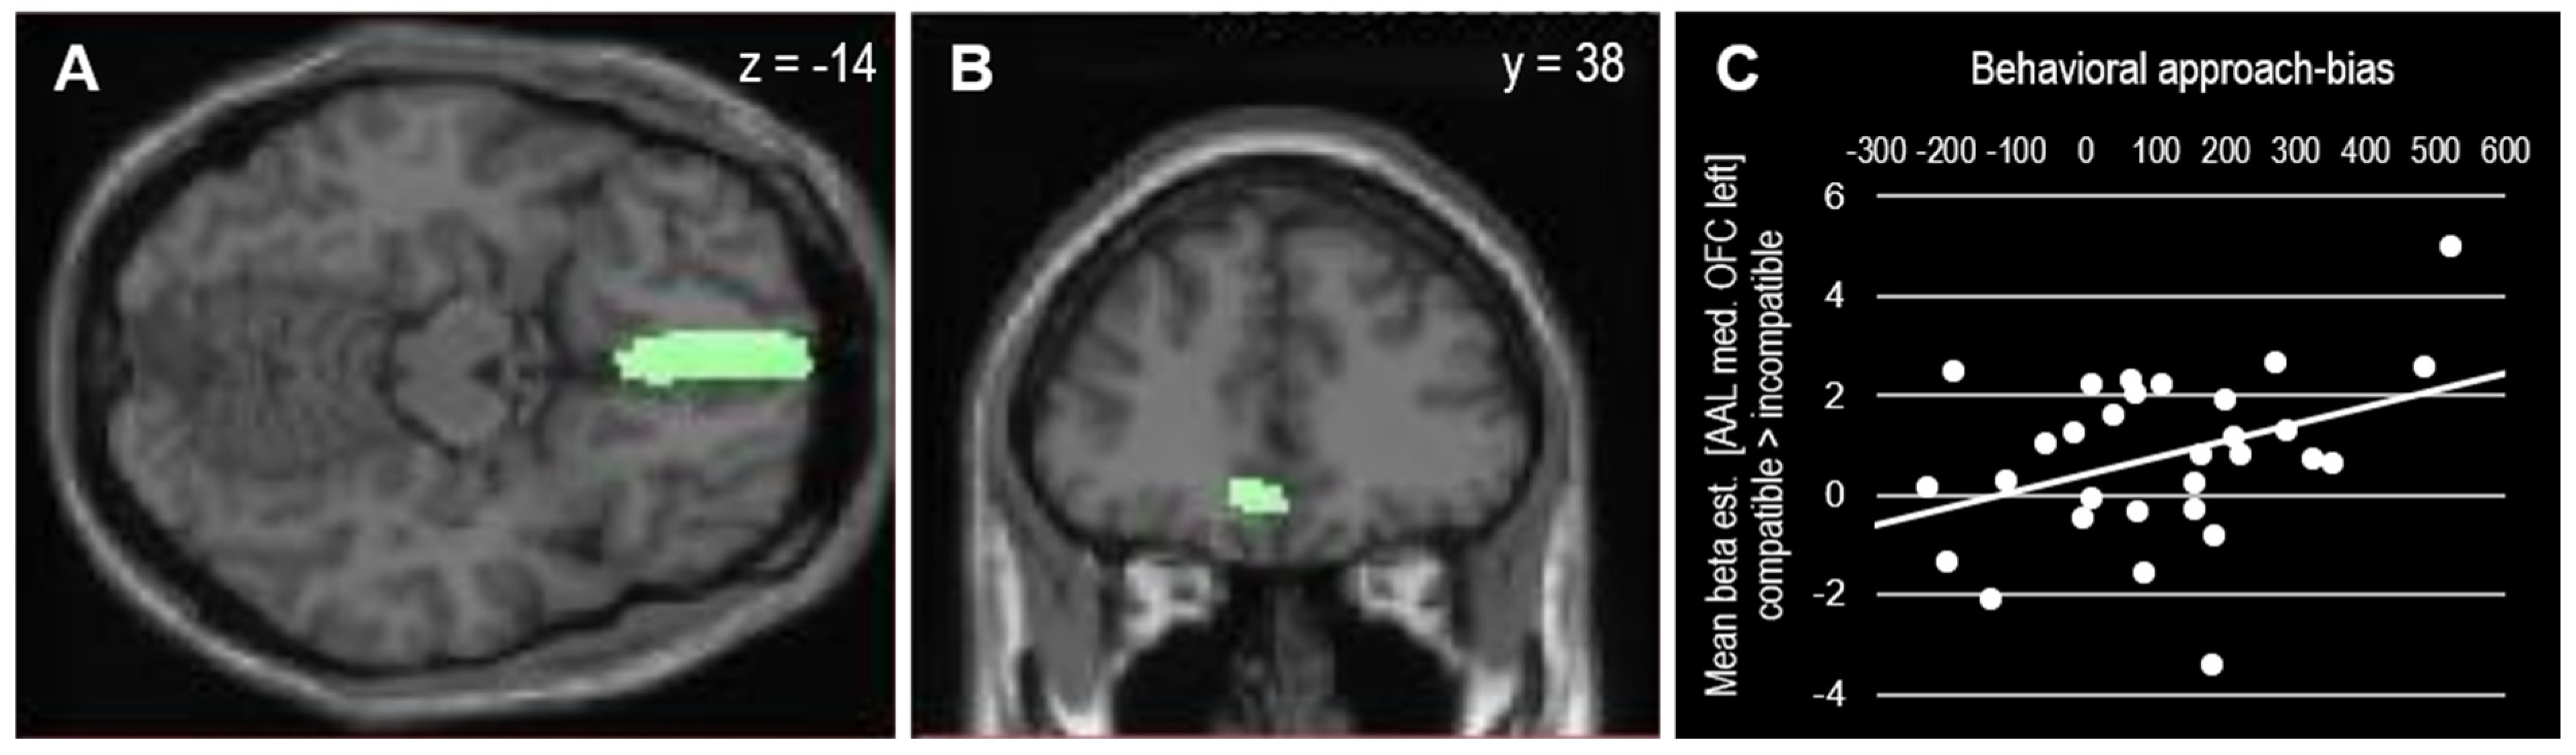

| Contrast | Brain Area | Voxels | MNI [x, y, z] | Tmax |

|---|---|---|---|---|

| Compatible > incompatible | ||||

| R medial occipitotemporal | 6 | 24, −76, −2 | 3.53 | |

| L medial orbitofrontal | 7 | −6, 38, −14 | 3.42 | |

| Incompatible > compatible | ||||

| L caudate nucleus | 7 | −6, −17, 7 | 4.05 |